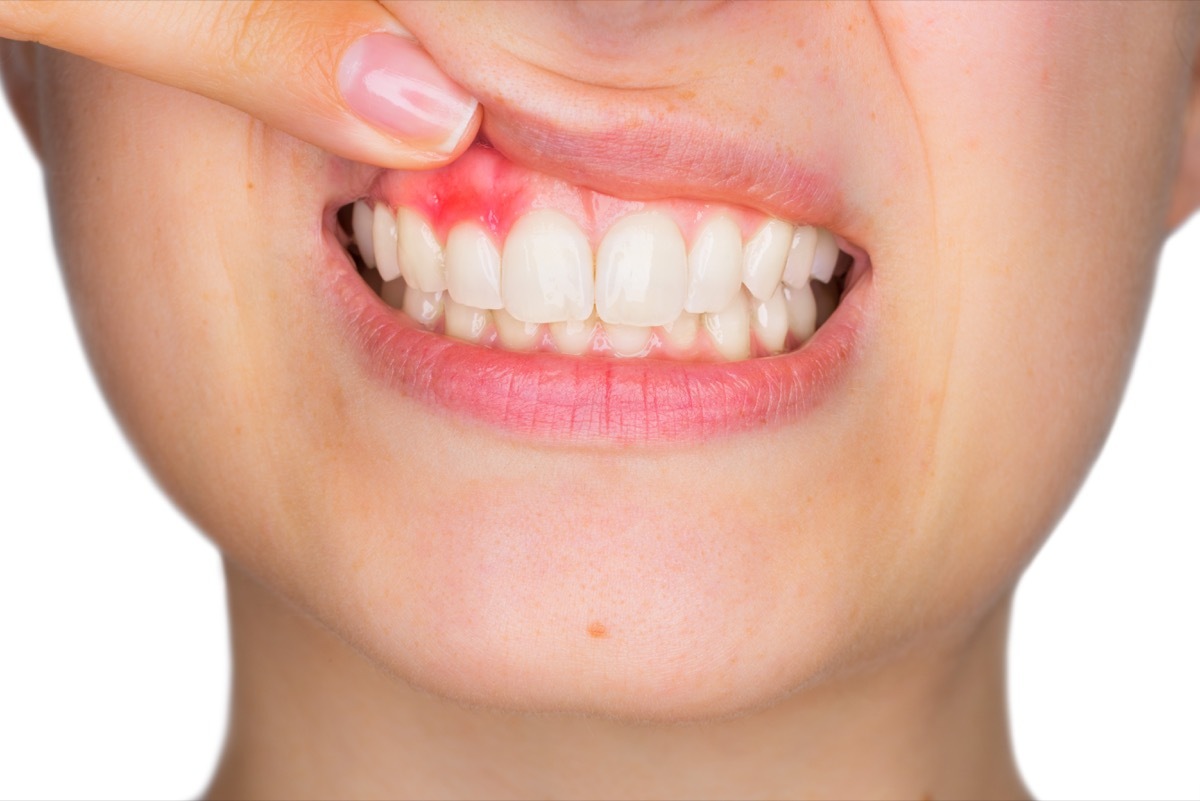

Ihr Gummis blutet, wenn Sie Zahnseide

Blutiges Zahnfleisch, während Zahnseide ein Zeichen der Zahnfleischerkrankung sein kann, ein Aufbau von Plaque und Bakterien auf dem Zahnfleisch, die dazu führen, dass Ihr Zahnfleisch von den Zähnen zurücktreten kann. LautUS-Außen- und Humanservice, die meisten Erwachsenen in den USA haben irgendeine Form dieser Krankheit, aber es ist wahrscheinlicher in Erwachsenen, die 30 bis 40 Jahre alt sind. In den milden Fällen führt es zu einem blutigen und leicht zurückhaltenden Zahnfleisch. In schweren Fällen kann es zu Zahnverlust und Zerfall führen.

Der rx: Mindestens zweimal täglich bürsten und einmal täglich ein Zahnseide (lügen Sie nicht Ihren Zahnarzt an! Sie weiß, wann Sie es tun!) Im Allgemeinen kann Gumerkrankungen verhindern. Ein professioneller tiefe Reinigung aller sechs Monate kann diese Krankheit auch in der Bucht halten. Wenn Ihre Zahnschmerzen mit blutigem Zahnfleisch verbunden sind, besuchen Sie Ihren Zahnarzt. Er oder sie kann eine zusätzliche mündliche Gesundheitsfürsorge wie einen täglichen Mundwasser oder ein Verfahren vorschlagen, um Ihre Zähne in schweren Fällen zu retten.